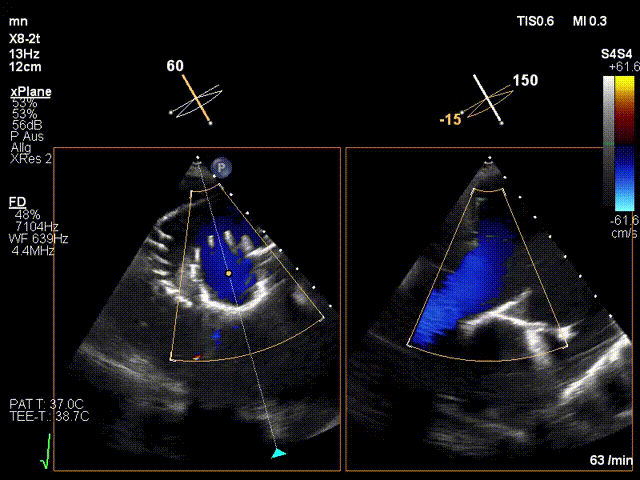

近日,德國(guó)慕尼黑大學(xué)Jörg Hausleiter教授團(tuán)隊(duì)成功應(yīng)用LuX-Valve Plus經(jīng)血管三尖瓣置換系統(tǒng)救治了一例因三尖瓣大量反流導(dǎo)致的右心衰竭患者,術(shù)后超聲顯示人工三尖瓣位置固定滿意,瓣架穩(wěn)定,無反流和瓣周漏?;颊咴谑中g(shù)室即刻拔除氣管插管,血流動(dòng)力學(xué)改善顯著,LuX-Valve Plus經(jīng)血管三尖瓣置換系統(tǒng)的治療效果優(yōu)異。

手術(shù)在全麻狀態(tài)下進(jìn)行。在加拿大圣保羅醫(yī)院的Anson Cheung教授的指導(dǎo)參與下,術(shù)者采用經(jīng)右側(cè)頸靜脈入路的方式將輸送器送入患者心臟內(nèi),在TEE及DSA引導(dǎo)下調(diào)整輸送器頭端角度,使得輸送器與三尖瓣瓣環(huán)平面垂直。在輸送器進(jìn)入右心室后釋放室間隔錨定裝置,而后釋放瓣葉夾持件(2個(gè)耳片結(jié)構(gòu))成垂直狀態(tài)。在TEE及DSA確定夾持件固定至三尖瓣葉根部且位于右室側(cè)后釋放人工瓣心房側(cè)盤片。隨后調(diào)整瓣膜同軸性以及室間隔錨定件位置(貼合室間隔),前推藏針管并固定,進(jìn)而釋放室間隔錨定裝置,并再次確認(rèn)瓣膜位置、穩(wěn)定性及同軸性,合攏輸送鞘后撤出輸送器,完成LuX-Valve Plus人工三尖瓣瓣膜的植入。

LuX-Valve Plus經(jīng)血管三尖瓣置換系統(tǒng)本次“出海”圓滿完成,術(shù)后Jörg Hausleiter教授對(duì)LuX-Valve Plus經(jīng)血管三尖瓣置換系統(tǒng)的器械性能和治療效果大為稱贊,認(rèn)為L(zhǎng)uX-Valve Plus的手術(shù)體驗(yàn)非常好。術(shù)后即刻超聲顯示三尖瓣反流消失,血流動(dòng)力學(xué)改善顯著,患者恢復(fù)快。Anson Cheung教授也肯定了LuX-Valve Plus術(shù)中操作的便捷性,認(rèn)為L(zhǎng)uX-Valve Plus容錯(cuò)率高,對(duì)術(shù)中影像的依賴較小,后期希望可以更多的應(yīng)用LuX-Valve Plus三尖瓣置換系統(tǒng)于臨床實(shí)踐,讓更多的三尖瓣重度反流患者盡早獲益,改善預(yù)后。